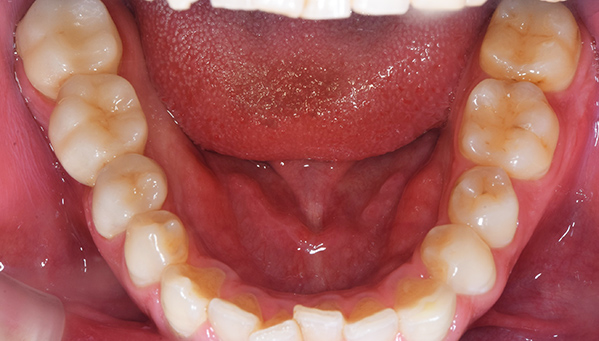

症例2

治療前

治療後

治療内容

奥歯はアマルガムという発ガン性があると言われている銀の素材を金銀シルバーインレーに変えました。前歯は金属を使用した歯でややまわりのご自身の歯より色がういていたので、周りの歯にあわせて透明感のある仕上がりのある材料にてやり変えました。

治療期間 1ヶ月

治療費 合計:990,000円 (内訳)

ジルコニアボンド:165,000円×6本

治療のリスク・副作用 被せ物を外すと、ご自身の歯が少ない場合は別途はを残すための処置が必要になることがあります。